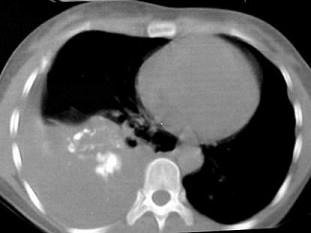

问题 男,66岁,剧烈胸痛,请结合CT图像,选择最可能的诊断 ( )

选项 A、右侧肺不张 B、右侧肺肺癌 C、右肺癌侵犯胸膜 D、右侧胸膜间皮瘤 E、右侧胸腔积液胸膜钙化

答案 D